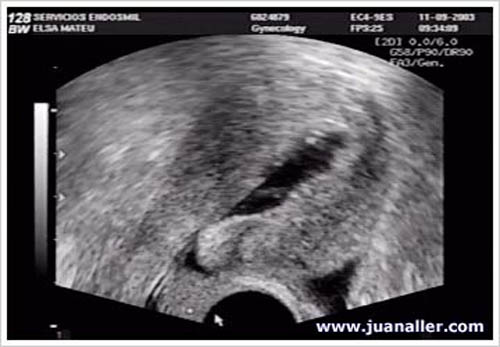

Diagnóstico. El ultrasonido convencional pudiera hacer sospechar un pólipo, pero lo más probable es que sea un endometrio normal de la etapa postovulatoria de un ciclo normal que se confunden con un pólipo. El diagnostico también se puede realizar por histerosalpingografia (HSG), donde se puede apreciar una imagen en el interior de la cavidad uterina, pero el diagnostico diferencial se tiene que hacer con un fibroma.

Ultrasonido e Histerosalpingografia con pólipo | |

La sonohisterografia (SHG) es muy bien tolerada, se realiza en el consultorio sin anestesia y brinda una excelente información del estado de la cavidad uterina. Es superior al que se obtiene con ultrasonido convencional o la HSG y similar al que se logra con la histeroscopia, que permite la visualización directa de la cavidad uterina mediante una fibra óptica.